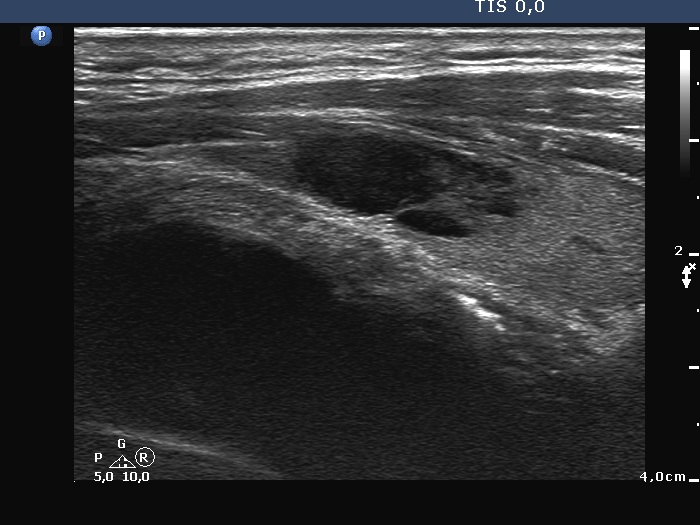

Right lobe, longitudinal scan

Left lobe, longitudinal scan. The lesion has deeply hypoechoic parts.